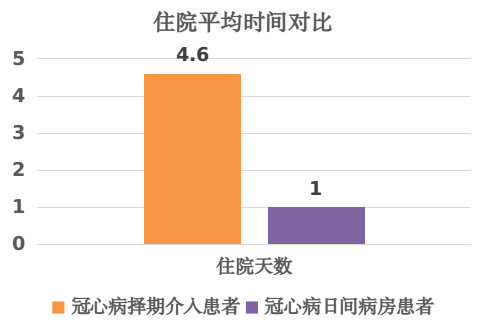

4.极大的降低了部分患者的经济负担、时间与精力的消耗,显著降低住院费用,减轻人民群众与政府的医疗负担。

在上级部门和领导的指导和支持下,冠心病介入“日间病房”模式得以迅速推广。通过严格的质量控制体系,确保手术的安全和有效,也确保住院当天术前准备和术后观察的高质量,极大的缩短了部分冠心病患者的就医时间和经济负担。同时,这种模式也需要患者具有良好的自我管理能力,积极配合医护人员的指导,共同为手术的成功和术后康复努力。

总之,冠心病介入“日间病房”模式是一种创新、务实、高效的医疗模式,为患者带来了福音。冠心病介入“日间病房”模式具备诸多优点,它在医疗领域拥有广泛的应用前景。随着医疗技术的不断进步以及人们健康意识的提高,这种高效率、低成本的医疗模式必将会受到越来越多医生和患者的青睐。在未来的发展中,我们相信这种模式将会得到更广泛的应用和推广,从而为更多的患者带来福音。

医务工作者不但需要去思考怎样去解决疾病本身的诊疗问题,还要努力在诊疗过程中提升效率与服务水平。我院心内科团队以此次患者的诊疗为契机,在广东省内率先针对合适的病人实行“冠脉介入手术当天出入院”的日间病房方案,在1天内完成临床诊疗工作和出入院,最大限度满足病人的健康需求和工作生活需求。这项基于自身技术自信基础上作出的优化和革新,从患者层面,患者以最舒适和便利的方式得到了高质量的冠心病综合治疗;从政府层面,老百姓以较低的费用接受了高质量的诊治,以更低的医疗支出提供了医疗保障。